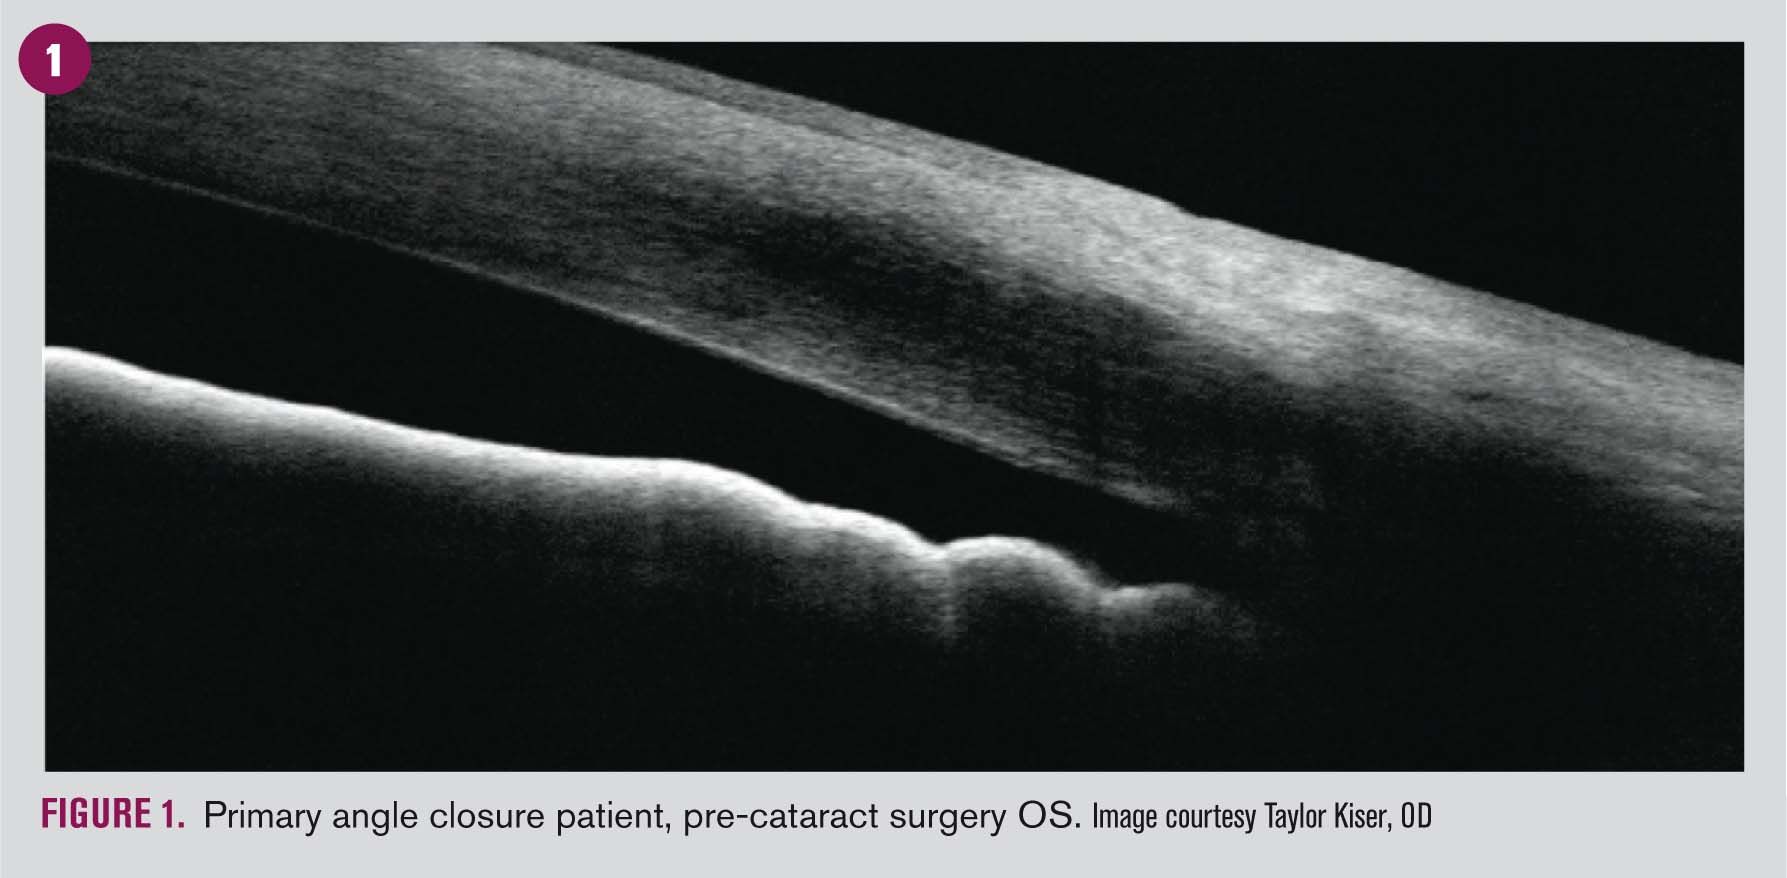

Angle OCT and ultrasound biomicroscopy are useful adjunct imaging tools but may not reveal important characteristics such as peripheral anterior synechiae and should not replace gonioscopic evaluation. Note that these adjunct tests do not yield information about the amount of pigment in the trabecular meshwork.

Angle OCT imaging is also helpful in monitoring angle position status post treatment as well as for patient education.

An alternative approach for managing PACG is surgical lens extraction, as used in managing age-related cataracts. Age-related growth of the lens plays a major part in the mechanisms leading to primary angle-closure glaucoma, and lens extraction is used routinely in patients with coexisting cataract.10

The effectiveness of early lens extraction for the treatment of primary angle-closure glaucoma (EAGLE) study is a step in determining the efficacy and safety of this treatment in people with primary angle-closure glaucoma without cataract. The results, released in 2016, showed that the study has achieved its primary aim to demonstrate that initial clear-lens extraction would be associated with better quality of life, lower IOP, and less need for glaucoma surgery at 36 months than standard care.19